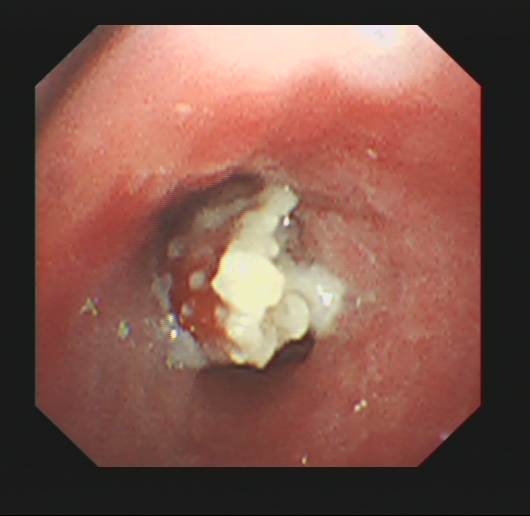

龚女士入院后,医生查看她的CT结果发现,龚女士病人右中叶支气管内有异物,为其安排了支气管镜检查,果然发现气道异物,揪出一块“辣椒皮”,辣椒皮周围已经形成增生的肉芽肿,而且有大量的化脓性感染,咳嗽半年多的罪魁祸首终于被找到。经过询问,龚女士仔细回忆,在半年前有次吃宵夜,是有呛咳的情况,但当时也没有多在意。